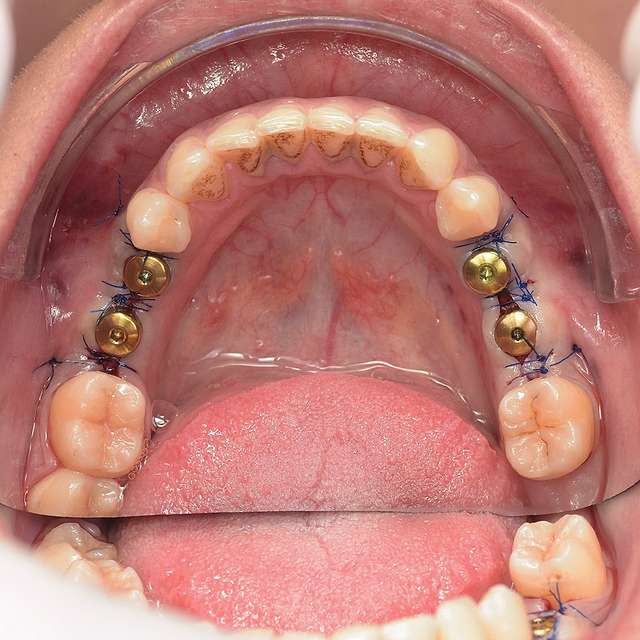

Ghidurile chirurgicale sunt utilizate pentru o siguranta si o precizie sporita in cazurile complexe care necesita tratamentul cu implanturi dentare. Ghidurile sunt printate 3D, conform planificarii digitale a chirurgiei, folosind un software specializat si radiografia 3D a pacientului. (computerul tomograf)

Pentru un rezultat estetic ideal, design-ul final trebuie sa fie intotdeauna referinta pentru chirurgie. Design-ul si computerul tomograf al pacientului sunt compilate pentru a primi pozitia ideala a implanturilor dentare

Chirurgia ghidata este sigura si precisa. Ghidul chirurgical este recomandat in cazurile cu un nivel ridicat de dificultate, sau in cazurile complexe, pentru a minimiza riscurile si complicatiile.

Cand procedura insertiei implanturilor dentare se realizeaza cu ajutorul chirurgiei ghidate, chirurgia in sine este mai simpla, iar trauma este mai redusa, in special asupra tesuturilor moi. Astfel, obtinem o vindecare mai rapida, si un comfort sporit post operator.